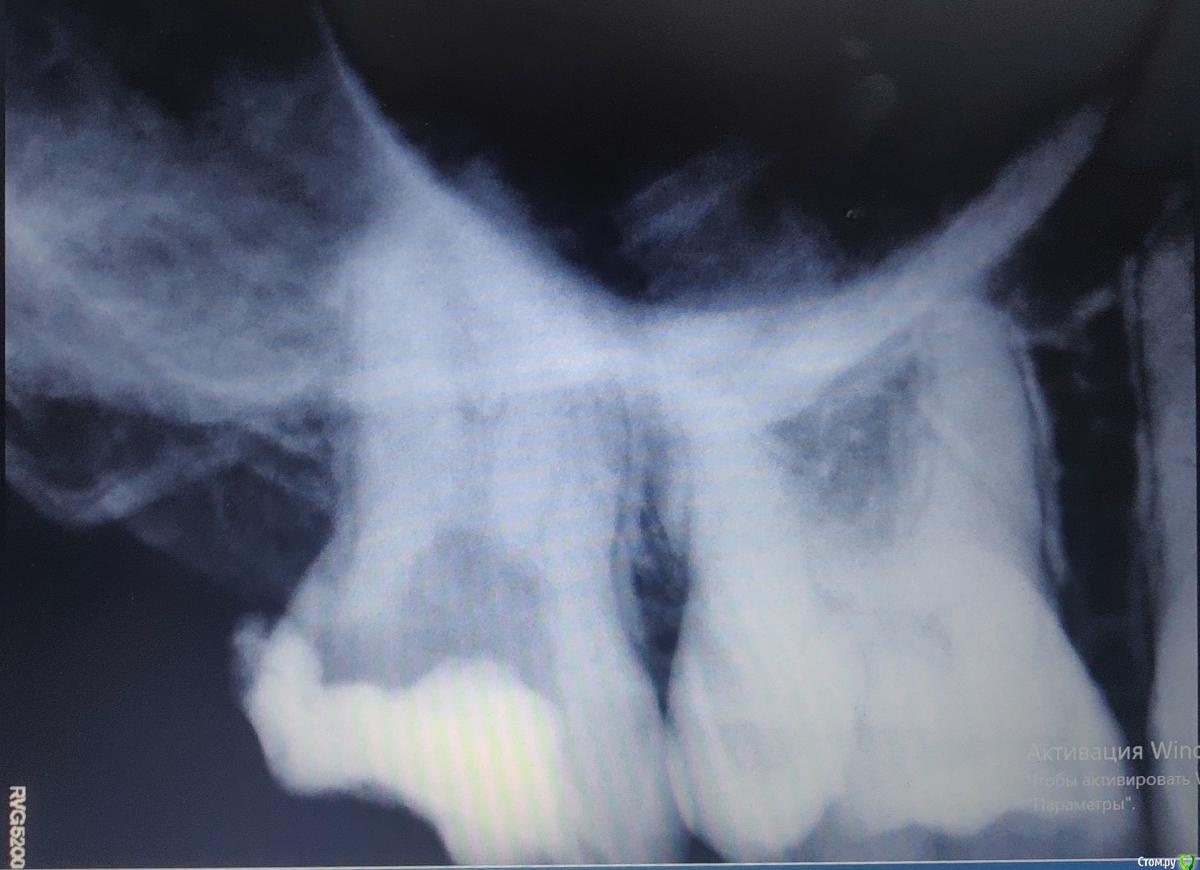

Рентген 17 зуба после расширения каналов, 13.10